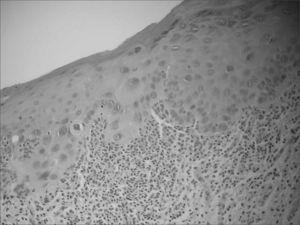

Figure 2 from Oral cancer and oral erythroplakia: an ...

Figure 2 from Oral cancer and oral erythroplakia: an ... from ai2-s2-public.s3.amazonaws.com

27: Erythroplakia (erythroplasia) | Pocket Dentistry

27: Erythroplakia (erythroplasia) | Pocket Dentistry from pocketdentistry.com